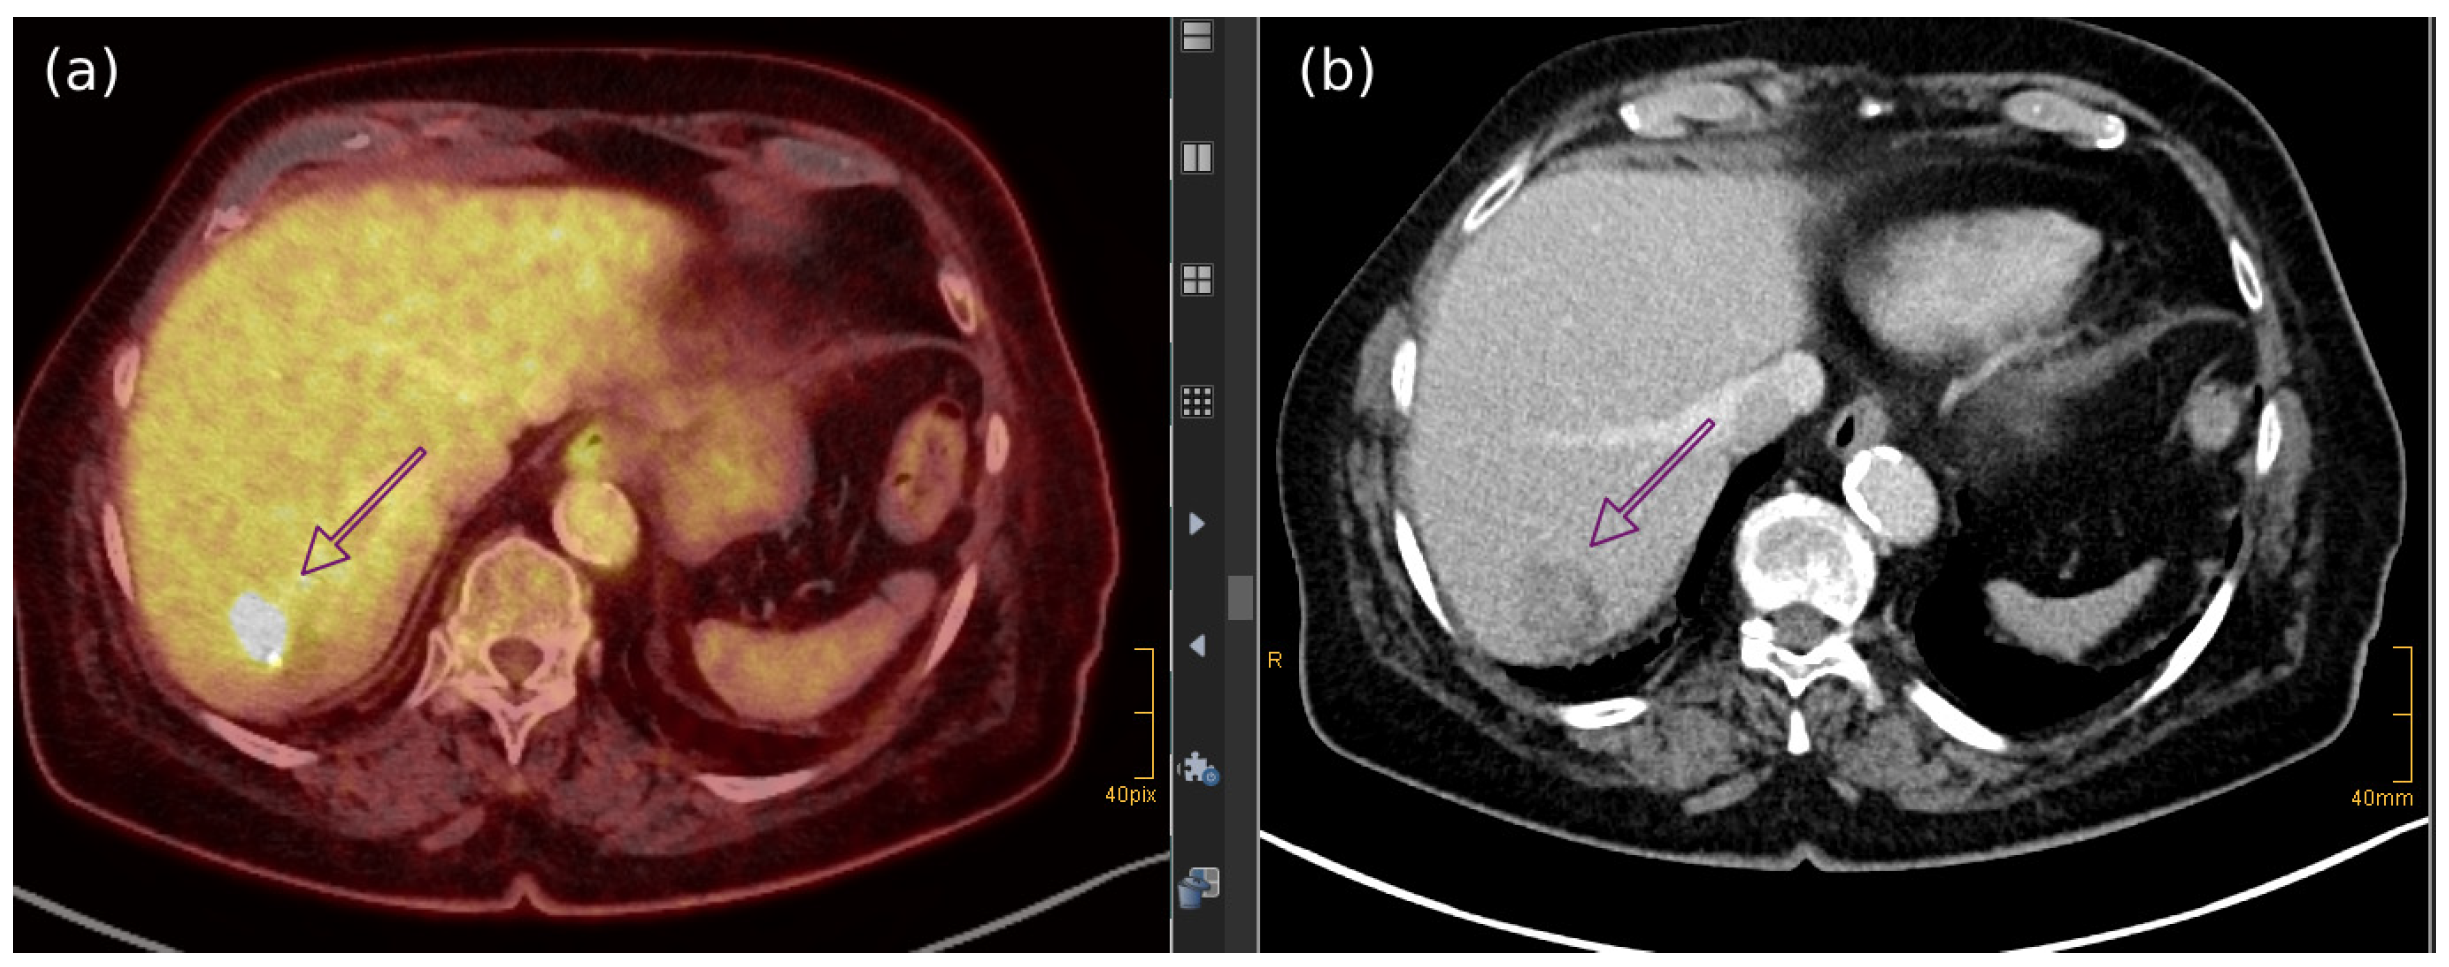

- Akaike, G.; Akaike, T.; Fadl, S.A.; Lachance, K.; Nghiem, P.; Behnia, F. Imaging of merkel cell carcinoma: What imaging experts should know. Radiographics 2019, 39, 2069–2084. [Google Scholar] [CrossRef]

- Oh, H.Y.; Kim, D.; Choi, Y.S.; Kim, E.K.; Kim, T.E. Merkel Cell Carcinoma of the Trunk: Two Case Reports and Imaging Review. J. Korean Soc. Radiol. 2023, 84, 1134–1139. [Google Scholar] [CrossRef]